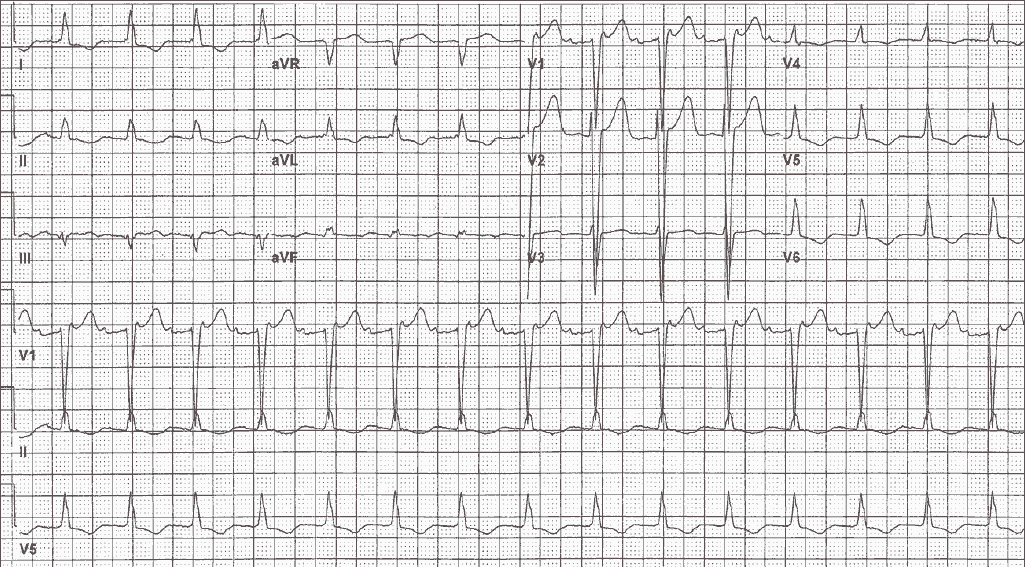

An 88-year-old man on digoxin presents to his cardiologist for routine follow-up. He is complaining of occasional palpitations and shortness of breath, and an ECG is obtained.

What is the arrhythmia?